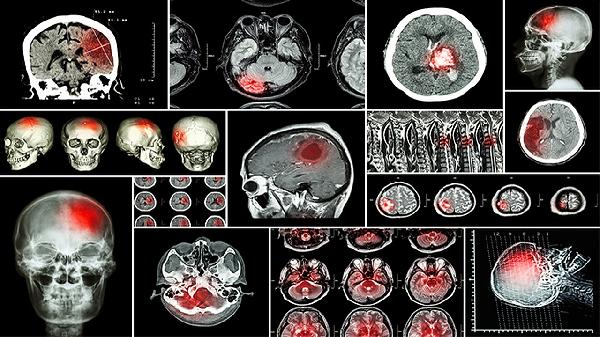

病毒性脑炎是一种由多种病毒引起的颅内感染,常见的病原体包括单纯疱疹病毒、肠道病毒、虫媒病毒、麻疹病毒和EB病毒等。这些病毒主要通过呼吸道、消化道、蚊虫叮咬、直接接触以及母婴垂直传播等方式进入人体。